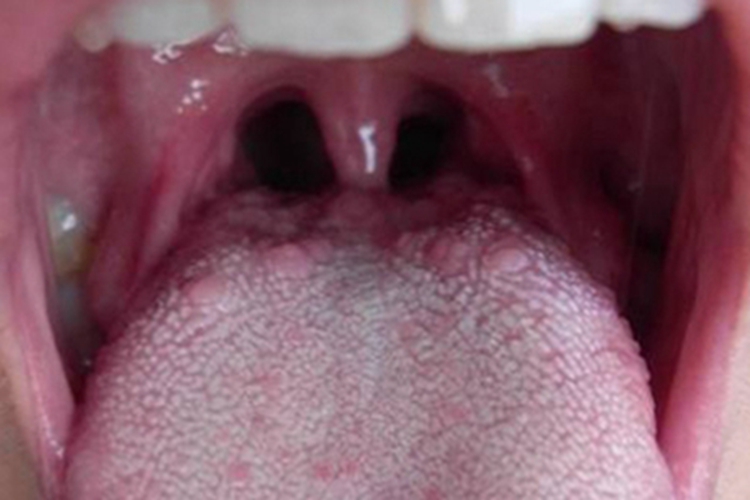

生理结构:舌背面黏膜呈淡红色,其表面可见许多小突起,呈小疙瘩样损害,统称为舌乳头,

轮廓乳头为舌背黏膜表面呈矮柱状的突起,是舌背乳头中体积最大者,数目最少,约有10个。叶状乳头为位于舌的两侧缘的后部的突起。

舌轮廓乳头炎:轮廓乳头发生炎症时,乳头肿大突起,呈小疙瘩样损害,轮廓清晰,表面发红,疼痛感不明显,少数患者有味觉迟钝。也有患者无意间发现并将其误认为肿瘤而感到恐惧。